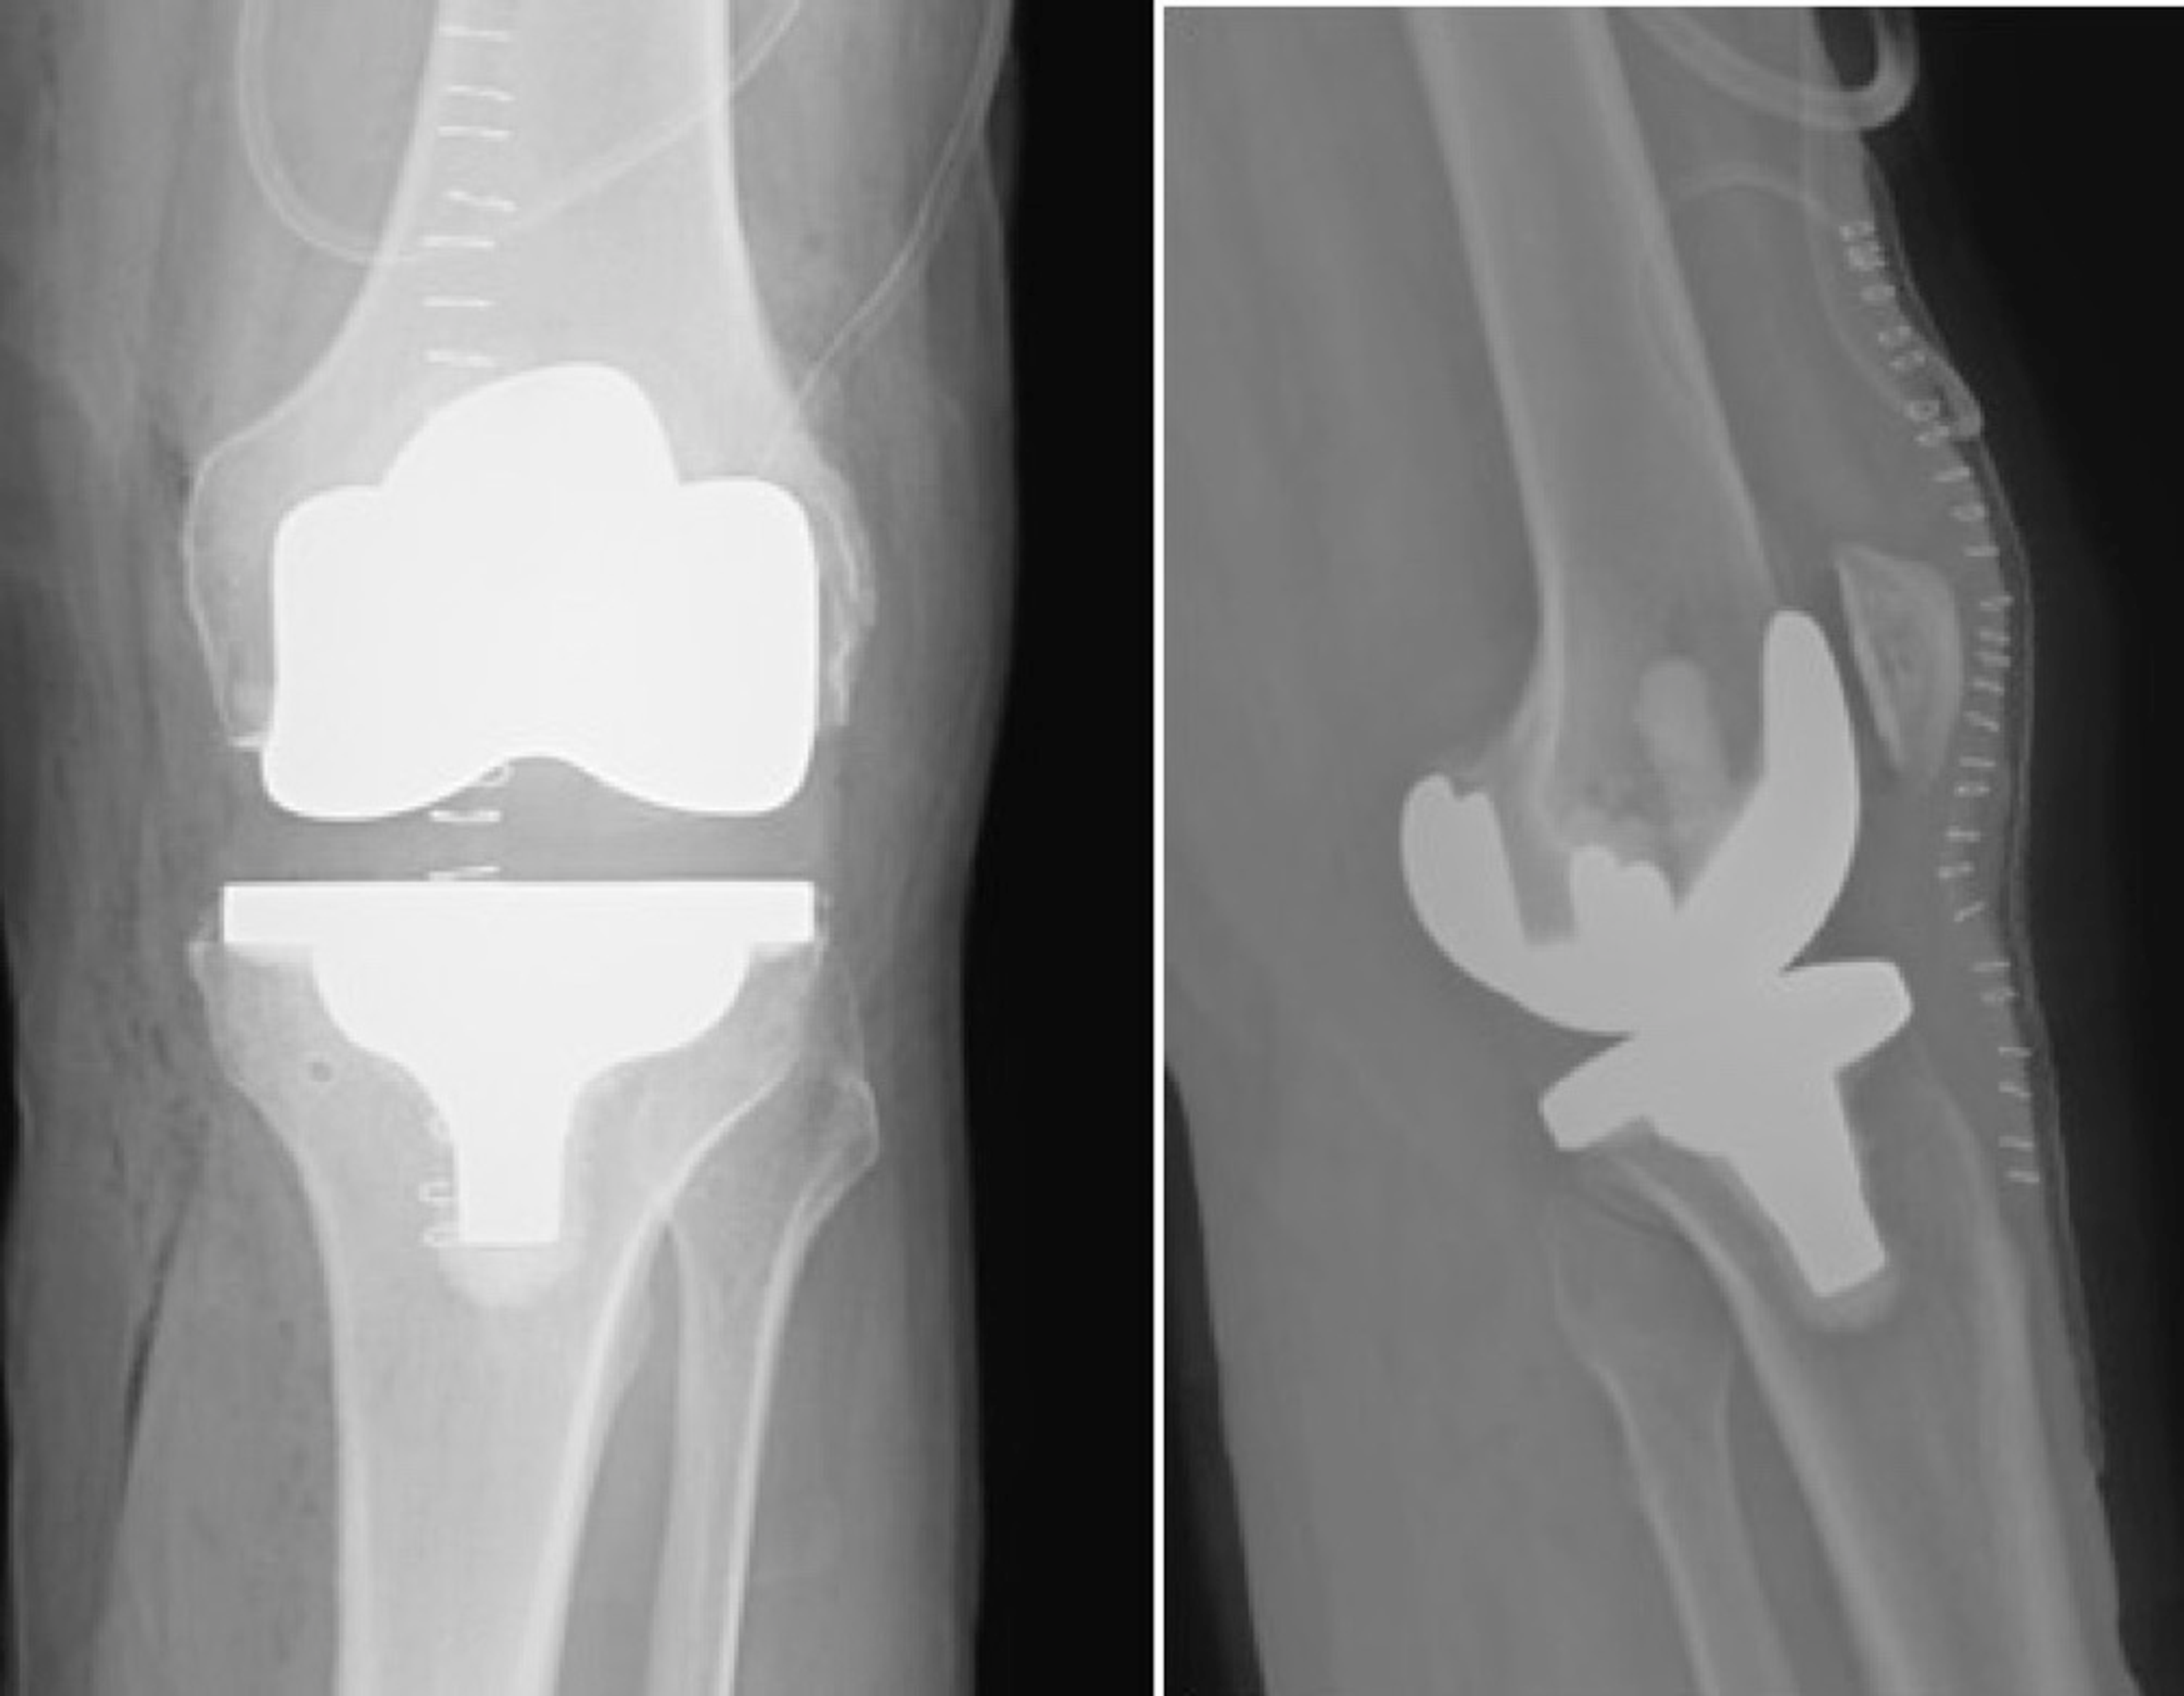

Components of Total Knee Arthroplasty. Precise resections are made in Cpt Code Total Knee Arthroplasty Performed when all three compartments of the knee are affected by. Proper documentation is crucial for coverage and reimbursement for this procedure. Cpt code 27447 is for a total knee arthroplasty, which is a surgical procedure that involves replacing the entire knee joint with an artificial. Total knee arthroplasty (also known as tka, or total knee replacement) : Medial and. Cpt Code Total Knee Arthroplasty.